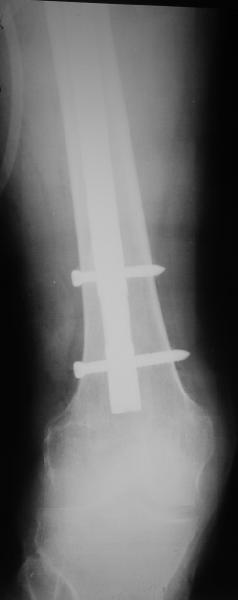

Спасибо за обсуждение. После нескольких дней тракции аппаратом сделали. Попытка закрытой репозиции не удалась из-за смещения по ширине, мешали фрагменты цемента. После их удаления репозиция получилась. Еще убрали немного цемента с ножки по латерльной стороне, чтобы обнажить 40-50 мм ее дистальной части, для плотной посадки гвоздя. Дальнейшее введение гвоздя было несложным. Протез показался нам стабильным в проксимальной части как латерально, так и медиально. Картинки в приложении.

THX for the discussion. After few days of traction by ex-fix the surgery was performed. An attempt of closed nailing was unsuccesful because of fragment translation, which was blocked by cement fragments. After removal of broken cement pieces reduction was reached "automagically". Also some cement from lateral part was removed by

chisel to expose distal 40-50 mm of the stem to allow tight fit of the nail. Further fixation by the nail was pretty easy and straightforward. Images attached. The stem looked stable in its proximal part both laterally and medially. Comments/critics are welcome.